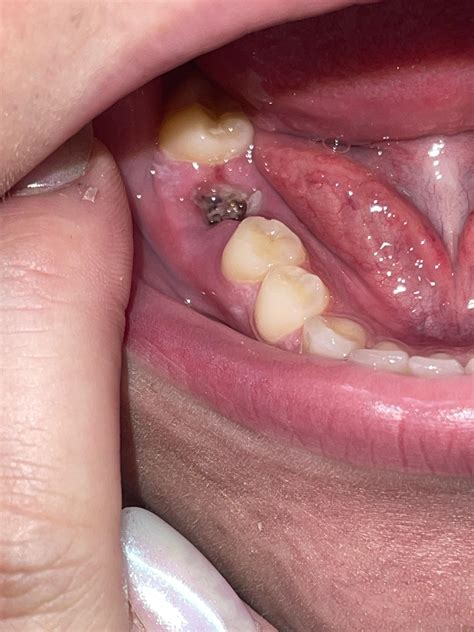

The period immediately following an infected tooth extraction is critical for preventing complications like "dry socket." A dry socket occurs when the protective blood clot that forms in the empty socket dislodges prematurely, exposing the nerves and bone. This is extremely painful and requires immediate attention from your dentist.

• infected tooth extraction site pictures

• Infected Tooth Socket